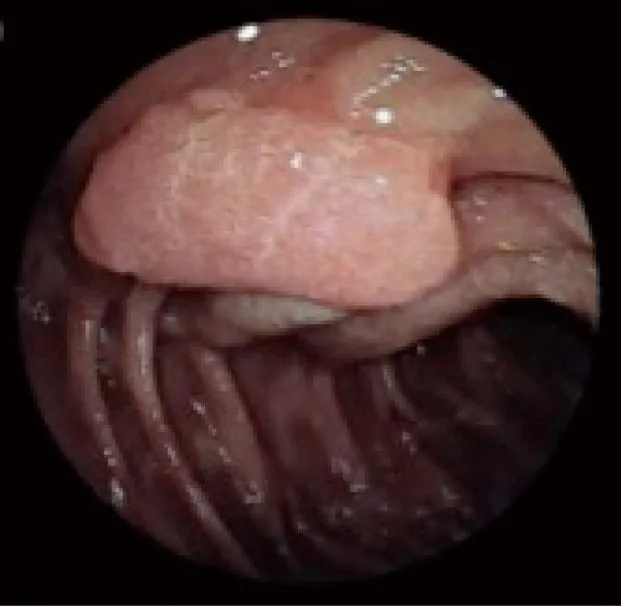

Рис. 3. Аденома двенадцатиперстной кишки 4-й стадии по Шпигельману [6].